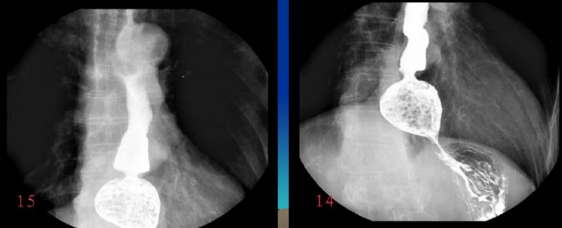

很多人沒(méi)有接觸到數(shù)字胃腸一體機(jī),可能對(duì)它還比較陌生。其實(shí)它是一款多功能數(shù)字造影胃腸機(jī),功能強(qiáng)大,操作便捷,可以真正實(shí)現(xiàn)數(shù)字化攝影,以及無(wú)膠片化管理,配置先進(jìn)的工作站,可以保證其圖像畫(huà)質(zhì)。同時(shí)它在臨床上的應(yīng)用也比較的廣泛,能夠檢查多種疾病。下面,由普愛(ài)醫(yī)療小編詳細(xì)列舉一些。

3、氣鋇雙重對(duì)比造影。